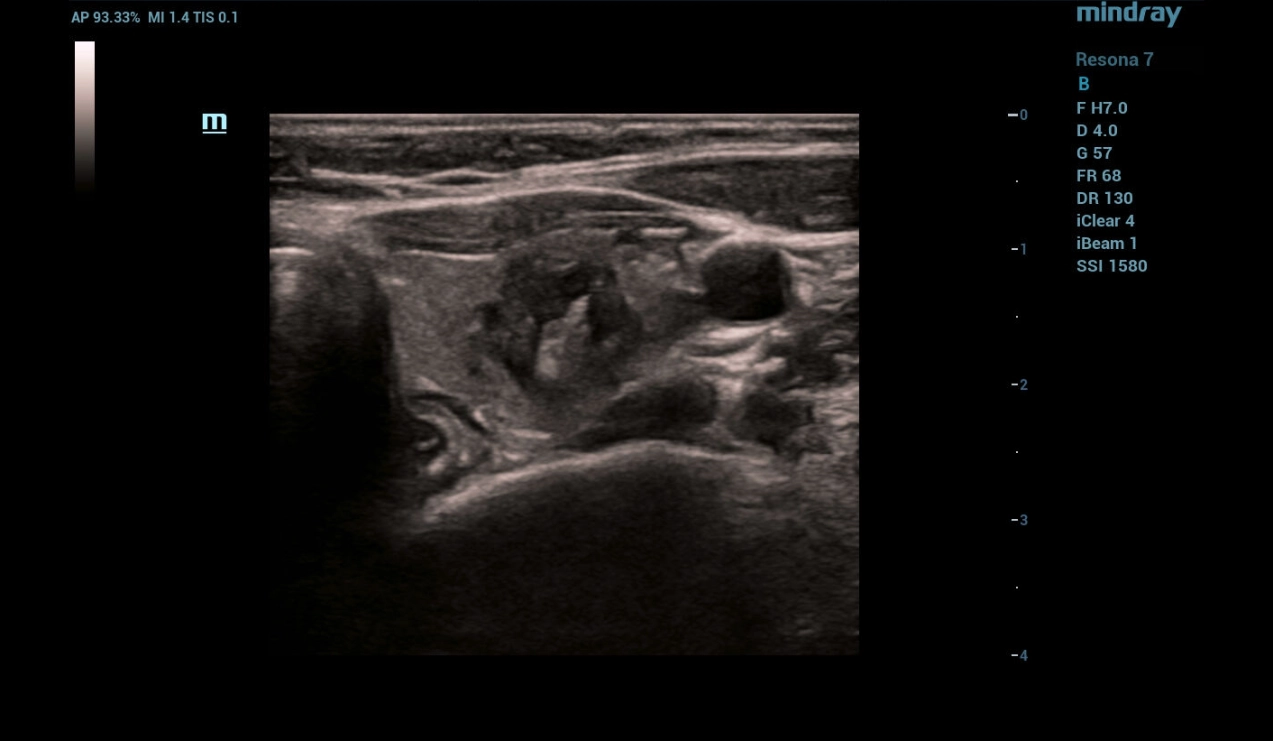

B-mode and Color Flow Doppler (CFD)

Ultrasonography was performed on a Resona 7 ultrasound machine (Mindray, China) using a linear probe L14-5WU. A cystic focal mass of anechogenic structure measuring 24x28x38 mm with smooth clear contours was detected in the left lobe of the thyroid gland (Fig. 1, 2)

throid-sclerotherapy-fig1-pc

Figure 1. B-mode image of the thyroid

Multiparametric ultrasound examination of the thyroid revealed a cystic focal mass in the left lobe without signs of malignancy.